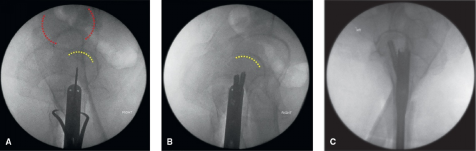

髋关节正位X线片应显示小转子轮廓,多数情况下可清晰显示梨状窝边界(红色标记)(图5)。

什么是c型臂术中透视骨科精读 | 股骨近端骨折的转子区域与矢状面力线术中透视技巧_https://www.jmylbn.com_新闻资讯_第5张

图5